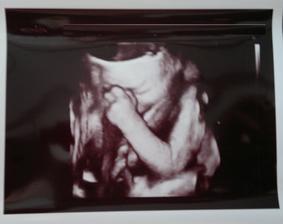

Jáchymek - -9. až 0. měsíc 🙂 - 2. těhotenství

Když se nám narodil náš milovaný Šimonek, řekli jsme si, že si ho chceme maximálně užít a že druhé miminko si pořídíme nejdříve za 5 až 6 let. Letí to jako blázen a Šimonkovi bude 5 let a tak jsme si řekli, že je ten správný čas 🙂 Začali jsme se snažit v říjnu 2013 a po třech měsících na nás vykoukly krásné // 🙂 První těhotenský test jsem si dělala 24. 12. 2013 a dala ho manželovi k Vánocům 🙂